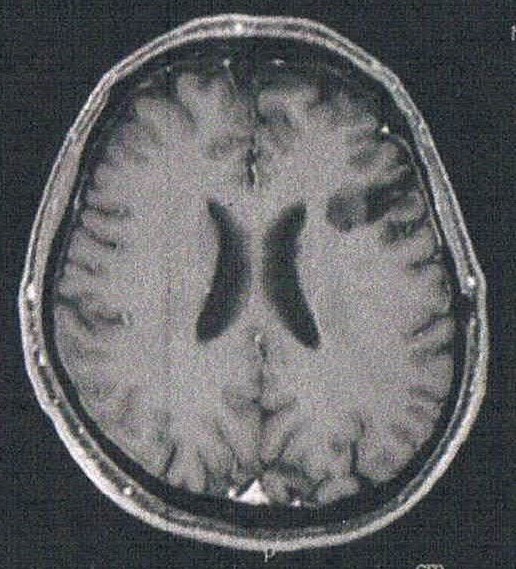

悪性転化しやすい腫瘍の種類(びまん性星細胞腫グレード2)であるとのことで造影剤を注射してMRI検査をする。4時間前から絶食し、MRIの1時間前に血液検査を済ませる。コロナで緊急事態宣言下であるからか院内は空いていて待ち時間は短い感じ。

診断の結果は特に変化はなく問題なし。造影剤がしみ込んでいる箇所もないとのことで、悪性度は低い状態を保っているとのこと。良かった!